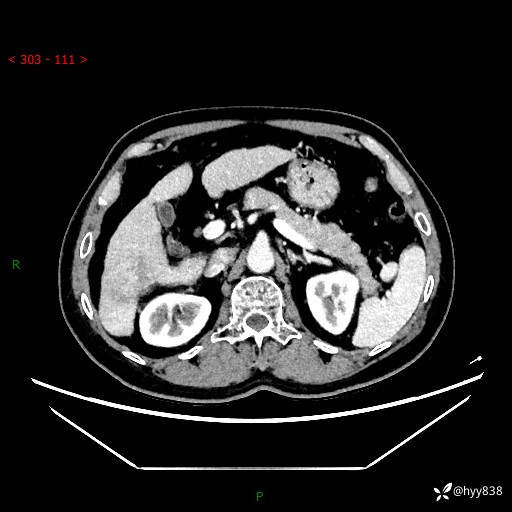

延迟期